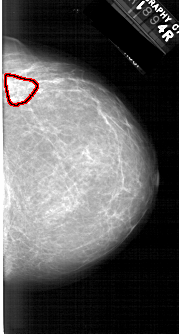

A_1610_1.RIGHT_CC

RIGHT_CC LINES 6001 PIXELS_PER_LINE 3211 BITS_PER_PIXEL 12 RESOLUTION 43.5 OVERLAY

FILE: A_1610_1.RIGHT_CC.OVERLAY

TOTAL_ABNORMALITIES 1

ABNORMALITY 1

LESION_TYPE MASS SHAPE ASYMMETRIC_BREAST_TISSUE MARGINS ILL_DEFINED

ASSESSMENT 4

SUBTLETY 3

PATHOLOGY BENIGN

TOTAL_OUTLINES 1

BOUNDARY